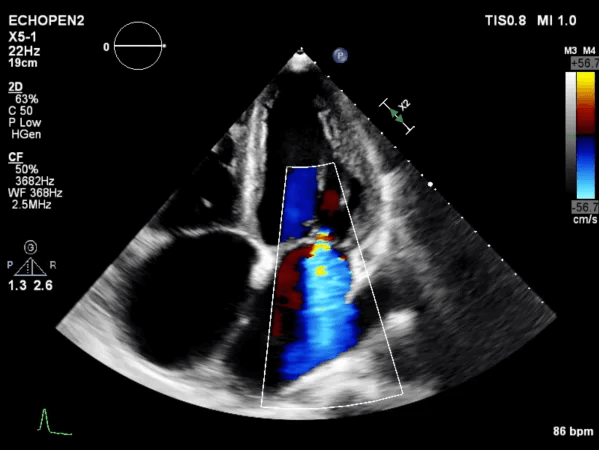

Transthoracic Echocardiogram

A transthoracic echocardiogram is an ultrasound that evaluates your heart's structure and function, providing detailed images to assess how well the heart muscle, valves, and chambers are working. It measures heart wall thickness, chamber size, and valve function, helping to detect any abnormalities. Doppler ultrasound is used to check blood flow, ensuring everything is circulating properly.

Transthoracic Echocardiogram Transthoracic Echocardiogram